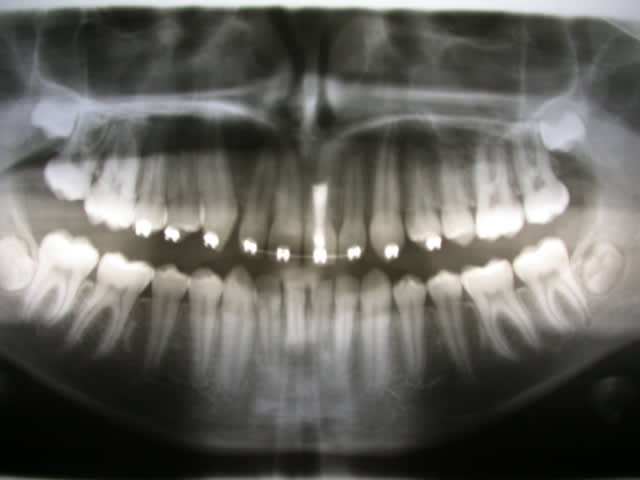

Patient de 14 ans, Classe II 1 par rétrognathie mandibulaire avec surplomb horizontal de 6mm. Pour n'avoir à déplacer 21 qu'un minimum, j'ai essayé de traiter la classe II avec un activateur mais le résultat a été médiocre. J'ai ensuite mis en place une mécanique de classe II sur multiattaches haut et bas, en souhaitant une avancée de l'arcade inférieure, mais, comme on se l'imagine, il y a aussi eu recul des secteurs latéraux supérieurs et il faudrait maintenant rétracter le bloc incisif supérieur.

Question: y a-t-il un risque (au niveau apical s'entend) à déplacer une incisive qui a subie une résection apicale?

Il y a toujours un risque de déplacer ce type de dent traitée par résection apicale.

Y-a-t'il eu une obturation rétrograde ?

Y-a-t'il un granulome à l'apex? Seul un cliché rétroalvéolaire te le dira.